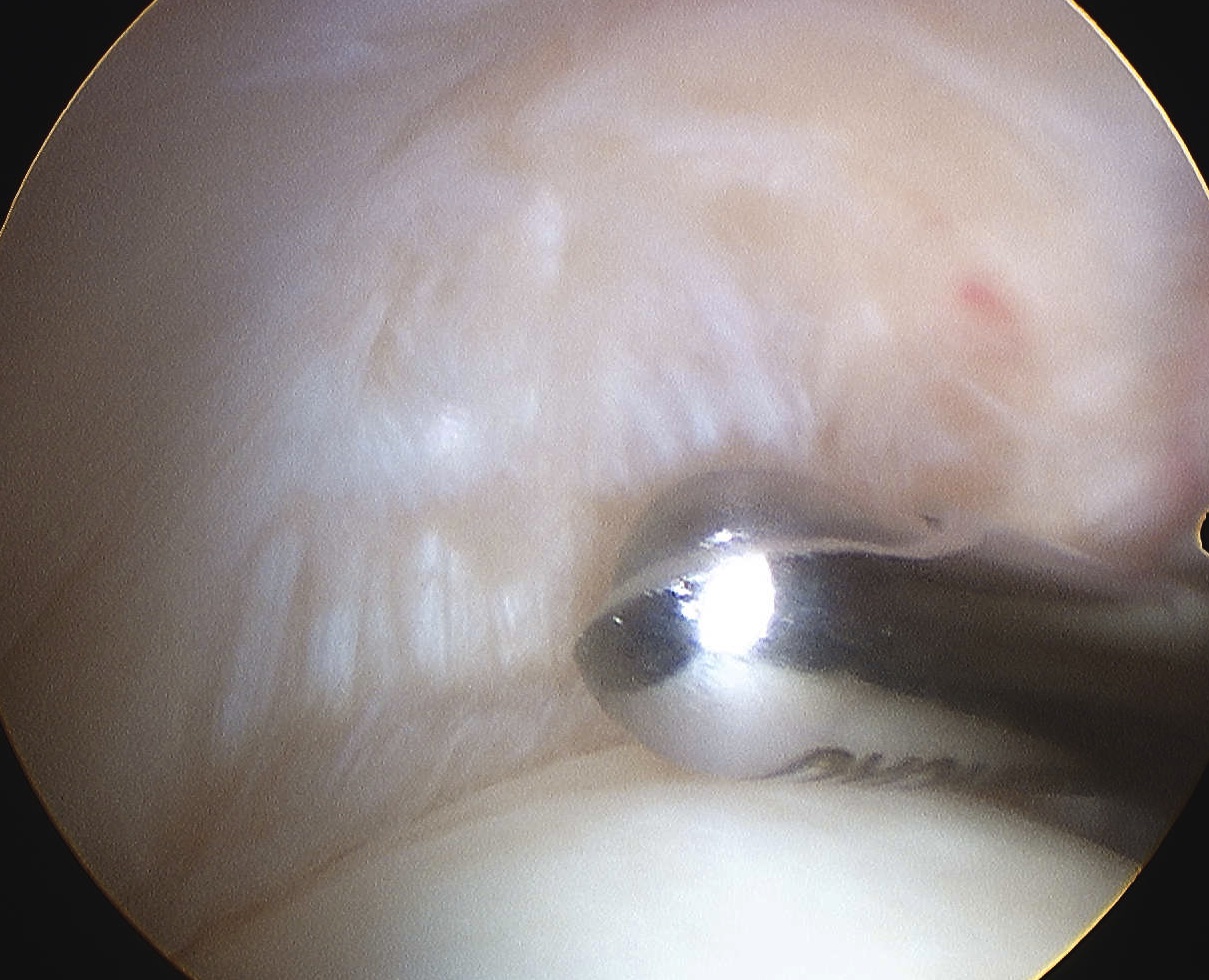

Undersurface supraspinatus - abduct arm

Infraspinatus / bare area / Hill Sachs

Subacromial space